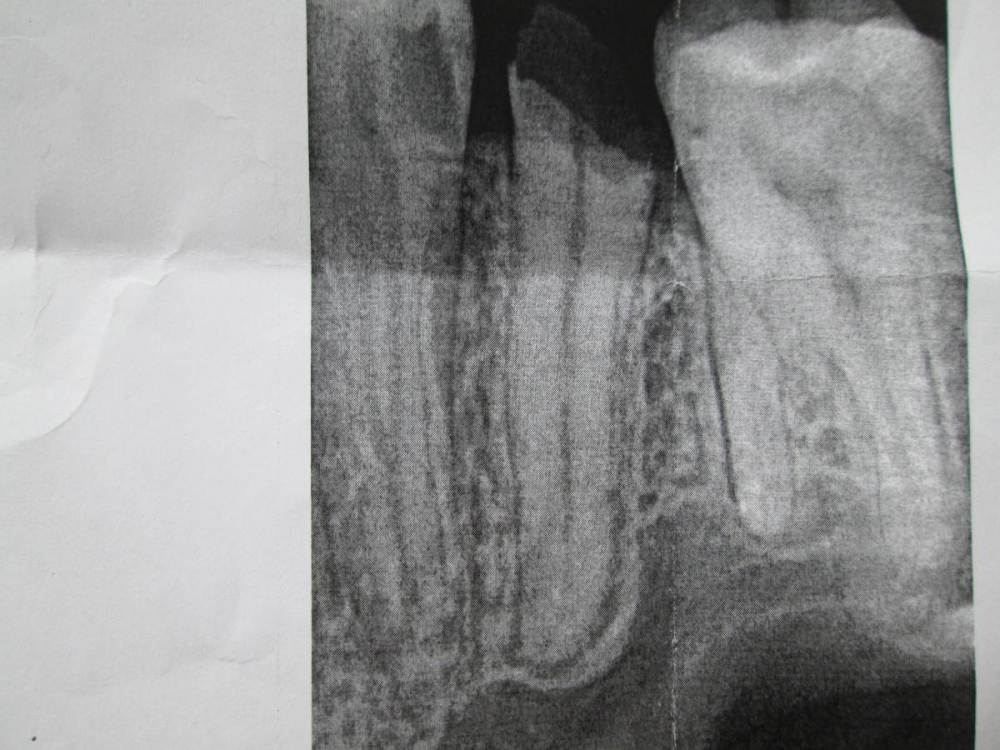

Nanny31 Опубликовано 29 апреля, 2021 Поделиться Опубликовано 29 апреля, 2021 Здравствуйте! Пару месяцев назад откололся премоляр (15-й), через месяц (работал) сходил в поликлинику. Сделали снимок, постучали, пожужжали, сказали удалять. Плюс насчитали 14 зубов к лечению. ОК. Один доктор хорошо, а два лучше. Пару дней назад, сходил в другую поликлинику, так же снимок (тот что меньше), итог - корень можно сохранить, метал. штифт + коронка. Плюс 8 зубов (на 6 меньше, предыдущего). Спросил про реставрацию, ничего не ответили, так же спросил про CEREC, тишина. Про реставрацию спросил не просто так. Уже был случай с моляром, было печальнее, но один врач сделал реставрацию, хотя другие так же говорили, что нужна коронка, штифт и т.д. Главное чтобы руки были прямые. Вопросы: 1. Что в данном случае будет оптимальным (коронка, реставрация, вкладка CEREC, что-нибудь иное)? 2. Перед анастезией дают ли направление на аллергопробу? Перед восстановлением моляра, была такая практика, частная клиника, но давали направление. Сейчас их уже нет. Ссылка на комментарий

red_butler Опубликовано 1 мая, 2021 Поделиться Опубликовано 1 мая, 2021 без очного осмотра ответить не получиться, возможно восстановление зуба потребует терапевтическую, ортодонтическую и/или хирургическую подготовку. Нсли судить только по рентгену, то удалять Ссылка на комментарий